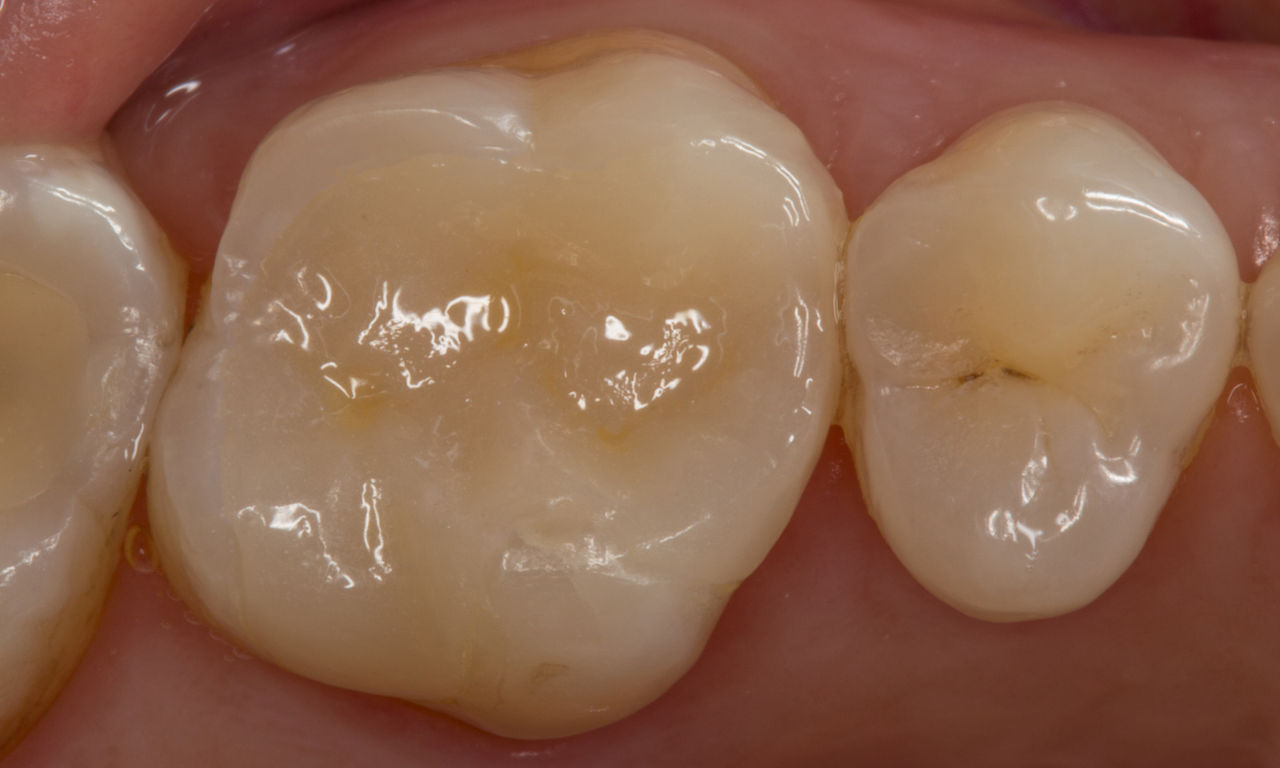

Second lower right molar in 90 minutes

A CEREC Tessera onlay

A 20-year-old female patient had endodontic treatment of her lower right 2nd molar. A chairside onlay was fabricated from the new high-strength ceramic CEREC Tessera ALD.

Before: Pre-operative clinical scenario after endodontic therapy.

After: 1 month after the CEREC Tessera onlay was bonded.

Dr. Aniruddha Nene

Pune, India